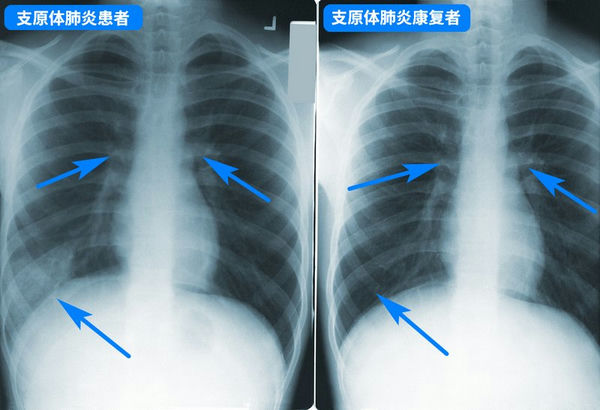

支原体肺炎胸透片

支原体肺炎一般并不严重,但要小心预防病情加重,尽早就医,如持续发烧5天以上、剧烈咳嗽不止,则一定要就医,以评估肺部是否受影响,以及是否存在并发症。治疗儿童支原体肺炎一般用阿奇霉素等大环内酯类药物,但因为亚洲地区滥用药物引起的耐药性问题,很可能效果不佳,需要在治疗过程中换药,具体应该遵医嘱。